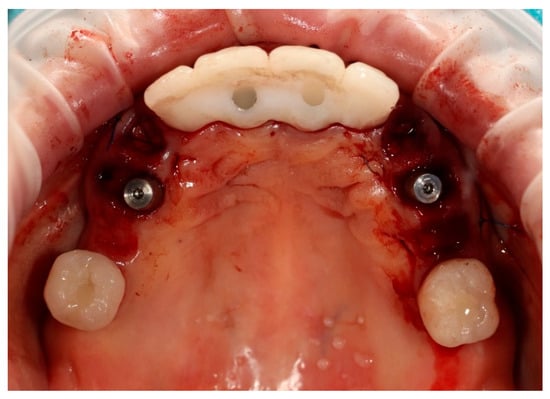

Simultaneously, the existing implant-supported crowns in positions 16 and 26, as well as the anterior implant-supported bridge, were unscrewed from the supporting implants. Multi-unit abutments were then selected and secured onto all six supporting implants, including the newly placed implants at sites 14 and 24 (Figure 4).

Figure 4. Multi-unit abutments secured onto all six supporting implants, including the newly placed implants at positions 14 and 24, following removal of the existing restorations.